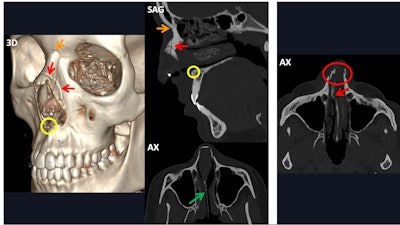

Due to its shape, the mandibular bone will often develop two different fractures: a primary one at the area of direct trauma and a secondary contralateral one due to force transmission, the researchers noted. The condition of the mandibular canal, the presence of basal triangles, and dentoalveolar fractures should be reported because surgery may be necessary, they added.

The images on the left side of the vertical white bar show a bilateral mandibular fracture. The left fracture (light yellowish-brown arrows) is located in the mandibular angle and crosses the mandibular canal, causing a fragment displacement of more than 5 mm (measurement in lower right image). The nondisplaced right fracture (orange arrows) is subtle in the parasymphyseal region, but it appears to involve the mental foramen. The images on the right side of the vertical white bar illustrate a bifocal left mandibular fracture. A comminuted and displaced (lower right image) fracture involves the symphyseal and parasymphyseal regions (orange arrows) and the mandibular body (lavender arrows) and crosses the mental foramen of the mandibular canal. The other fracture is a subcondylar luxation fracture (light blue arrows) with >35º angled fragments (light blue angle).